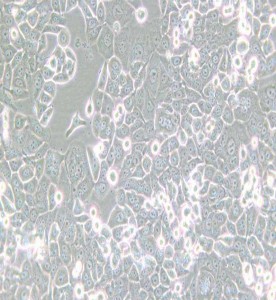

NCI-H2126人肺癌細胞

中文名稱 : 人肺癌細胞

細胞簡稱 : N CI-H 2126

細胞形態 : 上皮細胞樣

生長特性 : 貼壁細胞

培養環境 : 空氣,95% ;CO2,5% 37℃

凍存條件 : 55% 基礎培養基+40% FBS+5% D M SO液氮

完全培養基 : RPM I-1640(P M 150110)+10% FB S(164210-50)+1% P/S(PB 180120)

A n EBV -transform edlym phobla stoidcellline from thesam epatientis availa bleasN C I-BL2126.

倍增時間 ~57 hours(PBC F)

供體年齡 : 男;65歲

組織來源 : 肺腺癌,非小細胞肺癌;轉移部位:胸腔積液

細胞類型 : 腫瘤細胞

腫瘤類型 : 肺癌細胞

生物安全等級 : 1

致瘤性 : Yes,in nudemice(Tum orsdeveloped within onem onthin 4/5 nudemice

inoculated subcutaneouslywith 10^7 cells.)

細胞保藏中心 : ATCC ;  C C L-256